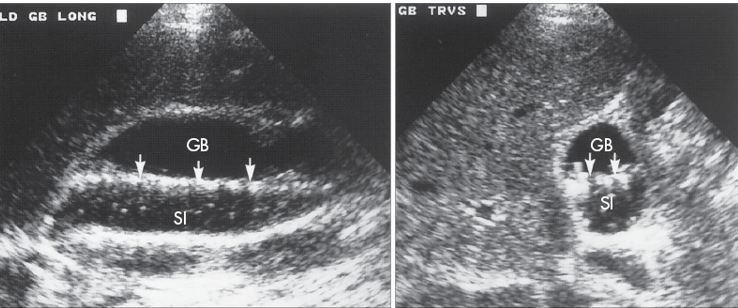

Sludge

This echogenic material has the following three characteristics

Does not cause shadowing

Is not gravity-dependent

Does not show a layering effect

patterns of sludge